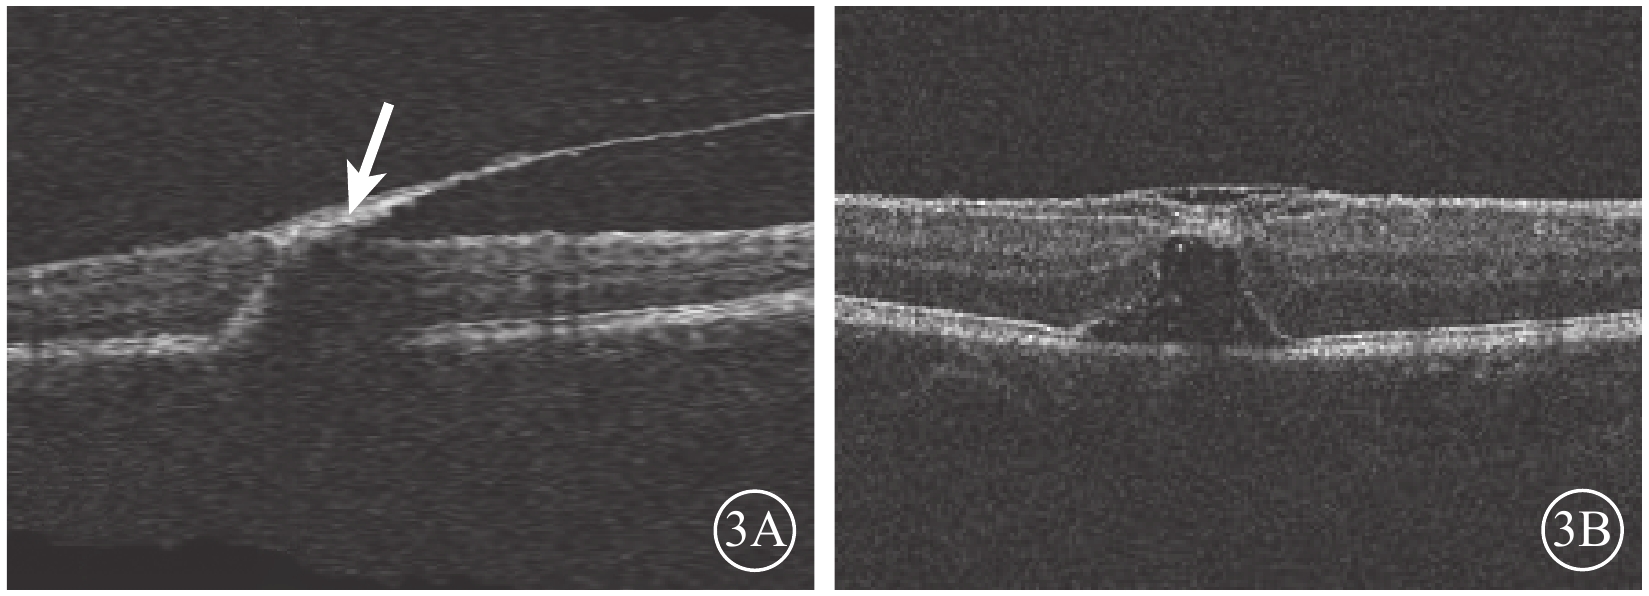

2015年12月7日行摻釹釔鋁石榴石(Nd:YAG)激光積血區內界膜(ILM)切開,最大能量3.5 mJ,單脈沖爆破模式,未見新鮮血液流出。未進行治療觀察。2016年1月27日復查,下方積血吸收邊緣至黃斑區(圖2A)。OCT檢查,黃斑區前ILM增厚,牽拉黃斑中心凹,黃斑正常結構消失(圖2B)。2月23日復查,右眼矯正視力0.25。黃斑區視網膜前出血基本吸收。OCT檢查,黃斑區ILM增厚,可見黃斑板層裂孔(圖3A)。4月20日復查OCT,黃斑中心凹處ILM增厚,中心凹鼻側ILM與其下視網膜組織分離,可見黃斑板層裂孔。仍未治療繼續觀察。8月17日復查,患者訴視物有水波紋樣浮動。OCT檢查,病變處ILM與其下視網膜組織分離,黃斑板層裂孔,黃斑中心凹處ILM較前略增厚(圖3B)。FFA檢查,黃斑拱環縮小,視網膜毛細血管變形稍紆曲,未見熒光素滲漏,可見線狀遮蔽熒光。

圖3

右眼OCT像。3A. 黃斑區ILM增厚,黃斑板層裂孔形成(白箭);3B. 黃斑區ILM與其下視網膜組織分離,黃斑區可見板層裂孔

圖3

右眼OCT像。3A. 黃斑區ILM增厚,黃斑板層裂孔形成(白箭);3B. 黃斑區ILM與其下視網膜組織分離,黃斑區可見板層裂孔

2015年12月7日行摻釹釔鋁石榴石(Nd:YAG)激光積血區內界膜(ILM)切開,最大能量3.5 mJ,單脈沖爆破模式,未見新鮮血液流出。未進行治療觀察。2016年1月27日復查,下方積血吸收邊緣至黃斑區(圖2A)。OCT檢查,黃斑區前ILM增厚,牽拉黃斑中心凹,黃斑正常結構消失(圖2B)。2月23日復查,右眼矯正視力0.25。黃斑區視網膜前出血基本吸收。OCT檢查,黃斑區ILM增厚,可見黃斑板層裂孔(圖3A)。4月20日復查OCT,黃斑中心凹處ILM增厚,中心凹鼻側ILM與其下視網膜組織分離,可見黃斑板層裂孔。仍未治療繼續觀察。8月17日復查,患者訴視物有水波紋樣浮動。OCT檢查,病變處ILM與其下視網膜組織分離,黃斑板層裂孔,黃斑中心凹處ILM較前略增厚(圖3B)。FFA檢查,黃斑拱環縮小,視網膜毛細血管變形稍紆曲,未見熒光素滲漏,可見線狀遮蔽熒光。

圖3

右眼OCT像。3A. 黃斑區ILM增厚,黃斑板層裂孔形成(白箭);3B. 黃斑區ILM與其下視網膜組織分離,黃斑區可見板層裂孔

圖3

右眼OCT像。3A. 黃斑區ILM增厚,黃斑板層裂孔形成(白箭);3B. 黃斑區ILM與其下視網膜組織分離,黃斑區可見板層裂孔